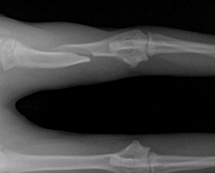

교통사고, 낙상으로 인해 발생하는 골절 정복을 골절의 유형과 환자의 상태를 고려하여 실시하고 있습니다. 고양이에서 골절이 잘 발생하는 위치는 하악골, 요/척골, 대퇴골, 사지 지골 등이 있으며, 고양이의 경우 장기간의 입원이 필요한 골절 수술 후에도 안정적인 입원 환경을 구축하여 환자의 빠른 회복을 돕고 있습니다.

• 골절 X-ray